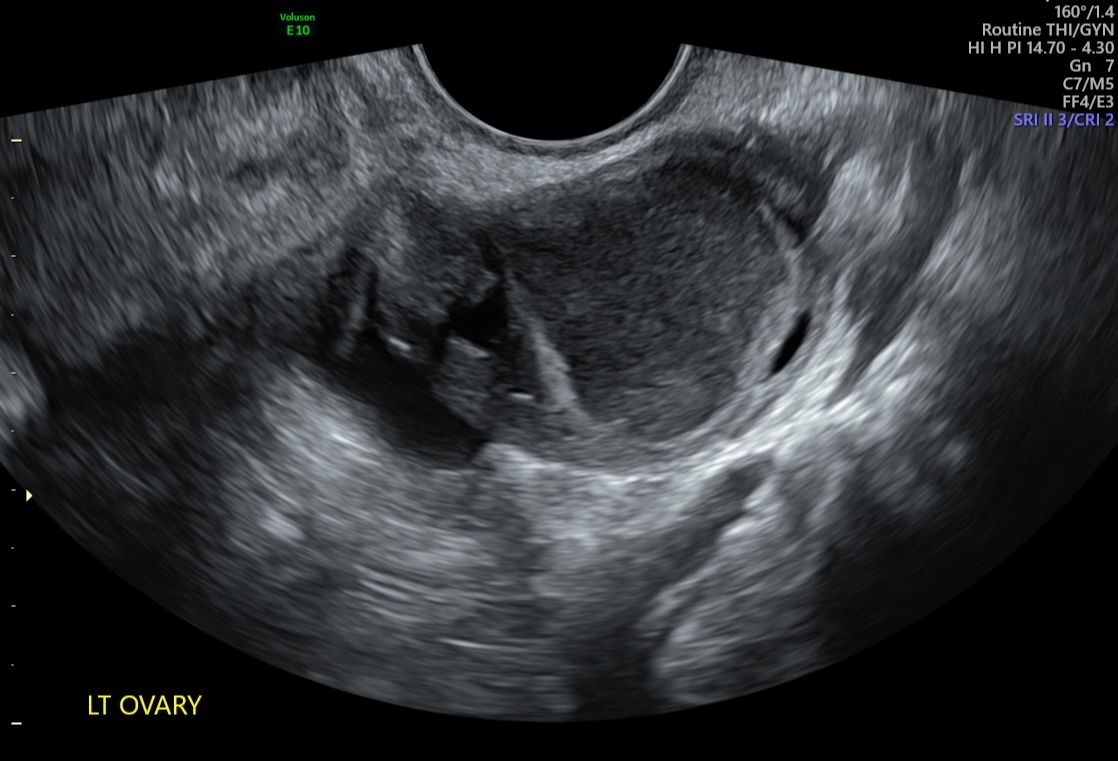

3D Uterus